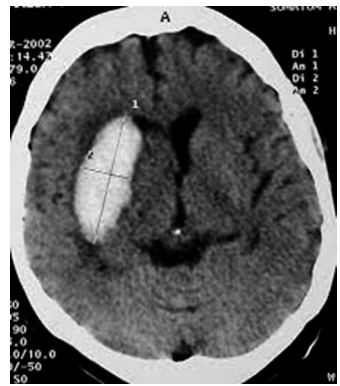

Homem de 67 anos, hipertenso de longa data e sem

acompanhamento médico regular, dá entrada no pronto-socorro com déficit motor súbito à esquerda, cefaleia

intensa e rebaixamento do nível de consciência. A tomografia computadorizada de crânio, encontra-se a seguir.

Qual das seguintes condutas é a mais apropriada nesse caso?